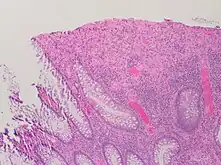

| A micrograph demonstrating cryptitis, a microscopic correlate of colitis. H&E stain. | |

An important investigation in the assessment of colitis is biopsy for histopathology. A very small piece of tissue (usually about 2mm) is removed from the bowel mucosa during endoscopy and examined under the microscope by a histopathologist. A biopsy report generally does not state the diagnosis, but should state any presence of chronic colitis, give an indication of disease activity, as well as state the presence of any epithelial damage (erosions and ulcerations).[4]

Histopathology findings generally associated with chronic colitis include:[4]

Crypt degeneration

Crypt branching and other architectural distortions

Paneth cell (pictured) or gastric metaplasia (only applies in the left colon and rectum)

Other findings include basal plasmacytosis and mucin depletion.[4] Histopathology findings generally associated with active colitis include:[4]

Neutrophilic cryptitis (neutrophils within crypt epithelium)

Crypt abscesses (luminal neutrophilic aggregates)

Gland destruction

Ulceration (seen here as absence of epithelium, and granulation tissue with many fibroblasts)